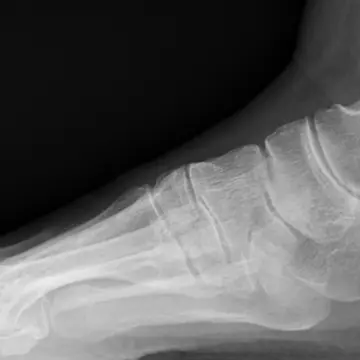

アキレス腱が柔軟だと、足底のアーチがくずれない。

アキレス腱が硬いと、足底を押しつぶし、偏平足に。